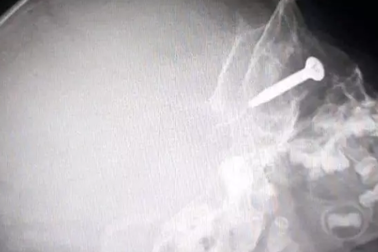

Tai nạn máy cắt cỏ, bé trai bị ốc vít cắm vào mắtMột cậu bé đến từ Thái Lan đã suýt bị mù sau khi chiếc máy cắt cỏ của cha vô tình cuốn phải một con ốc vít rồi văng vào mắt, đâm vào nhãn cầu của cậu bé.

Chiếc đinh ốc vít chui tọt vào dạ dày bé traiBé trai được đưa đến bệnh viện cấp cứu, sau khi người nhà phát hiện bé nuốt phải một chiếc đinh ốc vít.

Cả nhà hoảng loạn vào viện sau tiếng la “mẹ ơi, em nuốt ốc vít rồi”“Mẹ ơi, em nuốt ốc vít rồi” - tiếng la thất thanh của con trai lớn khiến vợ chồng chị T. giật mình hốt hoảng. Không kịp suy nghĩ nhiều, cả nhà lập tức đưa bé trai đến bệnh viện cấp cứu.

Cháu bé 19 tháng tuổi nuốt ốc vít sắc nhọn vào dạ dàyTrong lúc chơi đùa tại nhà, cháu bé 19 tháng tuổi ở Ninh Bình không may nuốt phải dị vật kim loại là chiếc ốc vít dài 1,5cm có đầu sắc nhọn vào dạ dày.